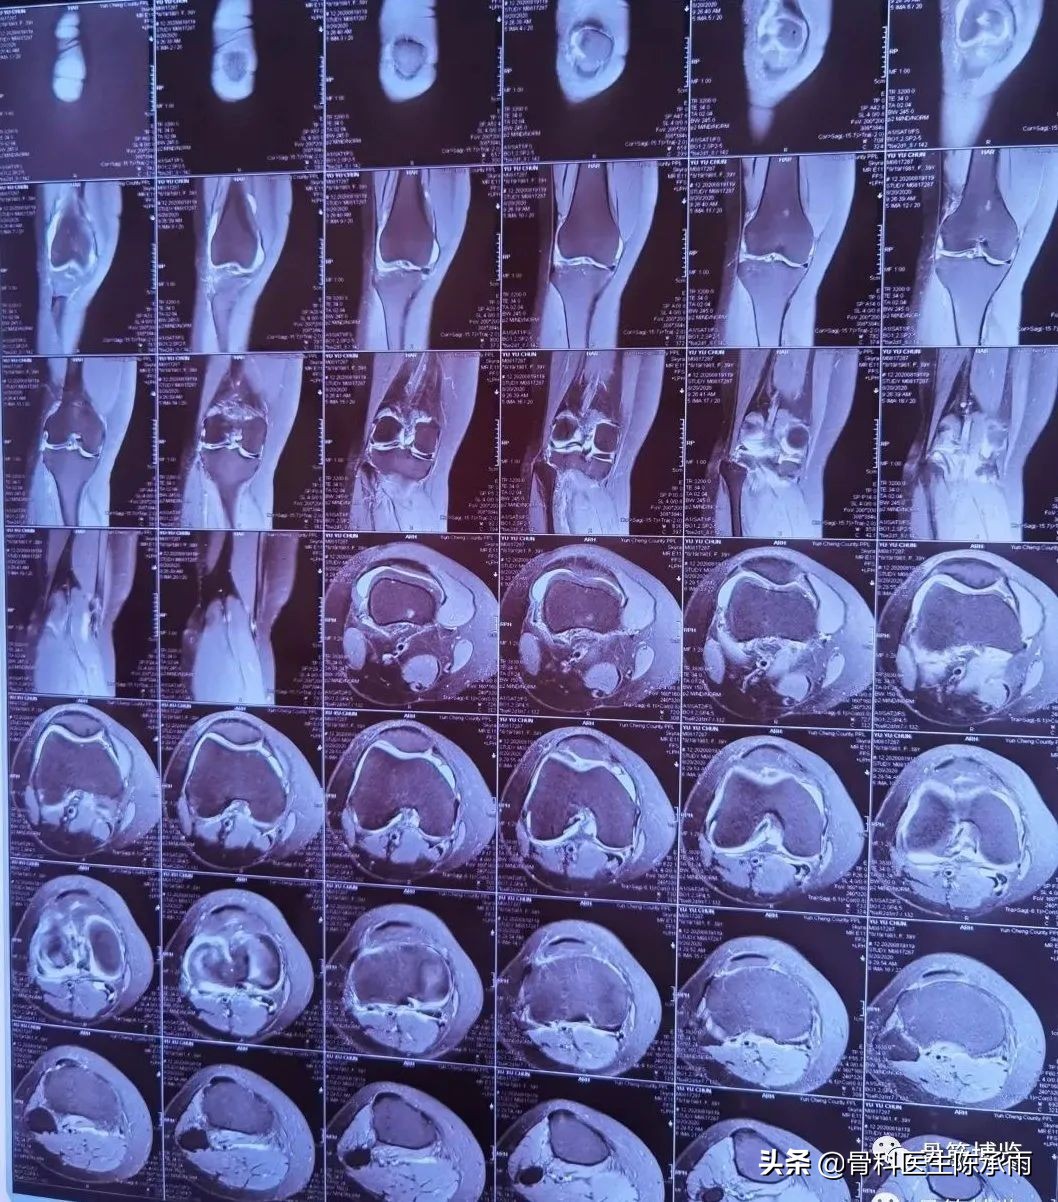

胫骨平台粉碎性骨折脱位半月板脱位罕见病例

图片尺寸4096x3072